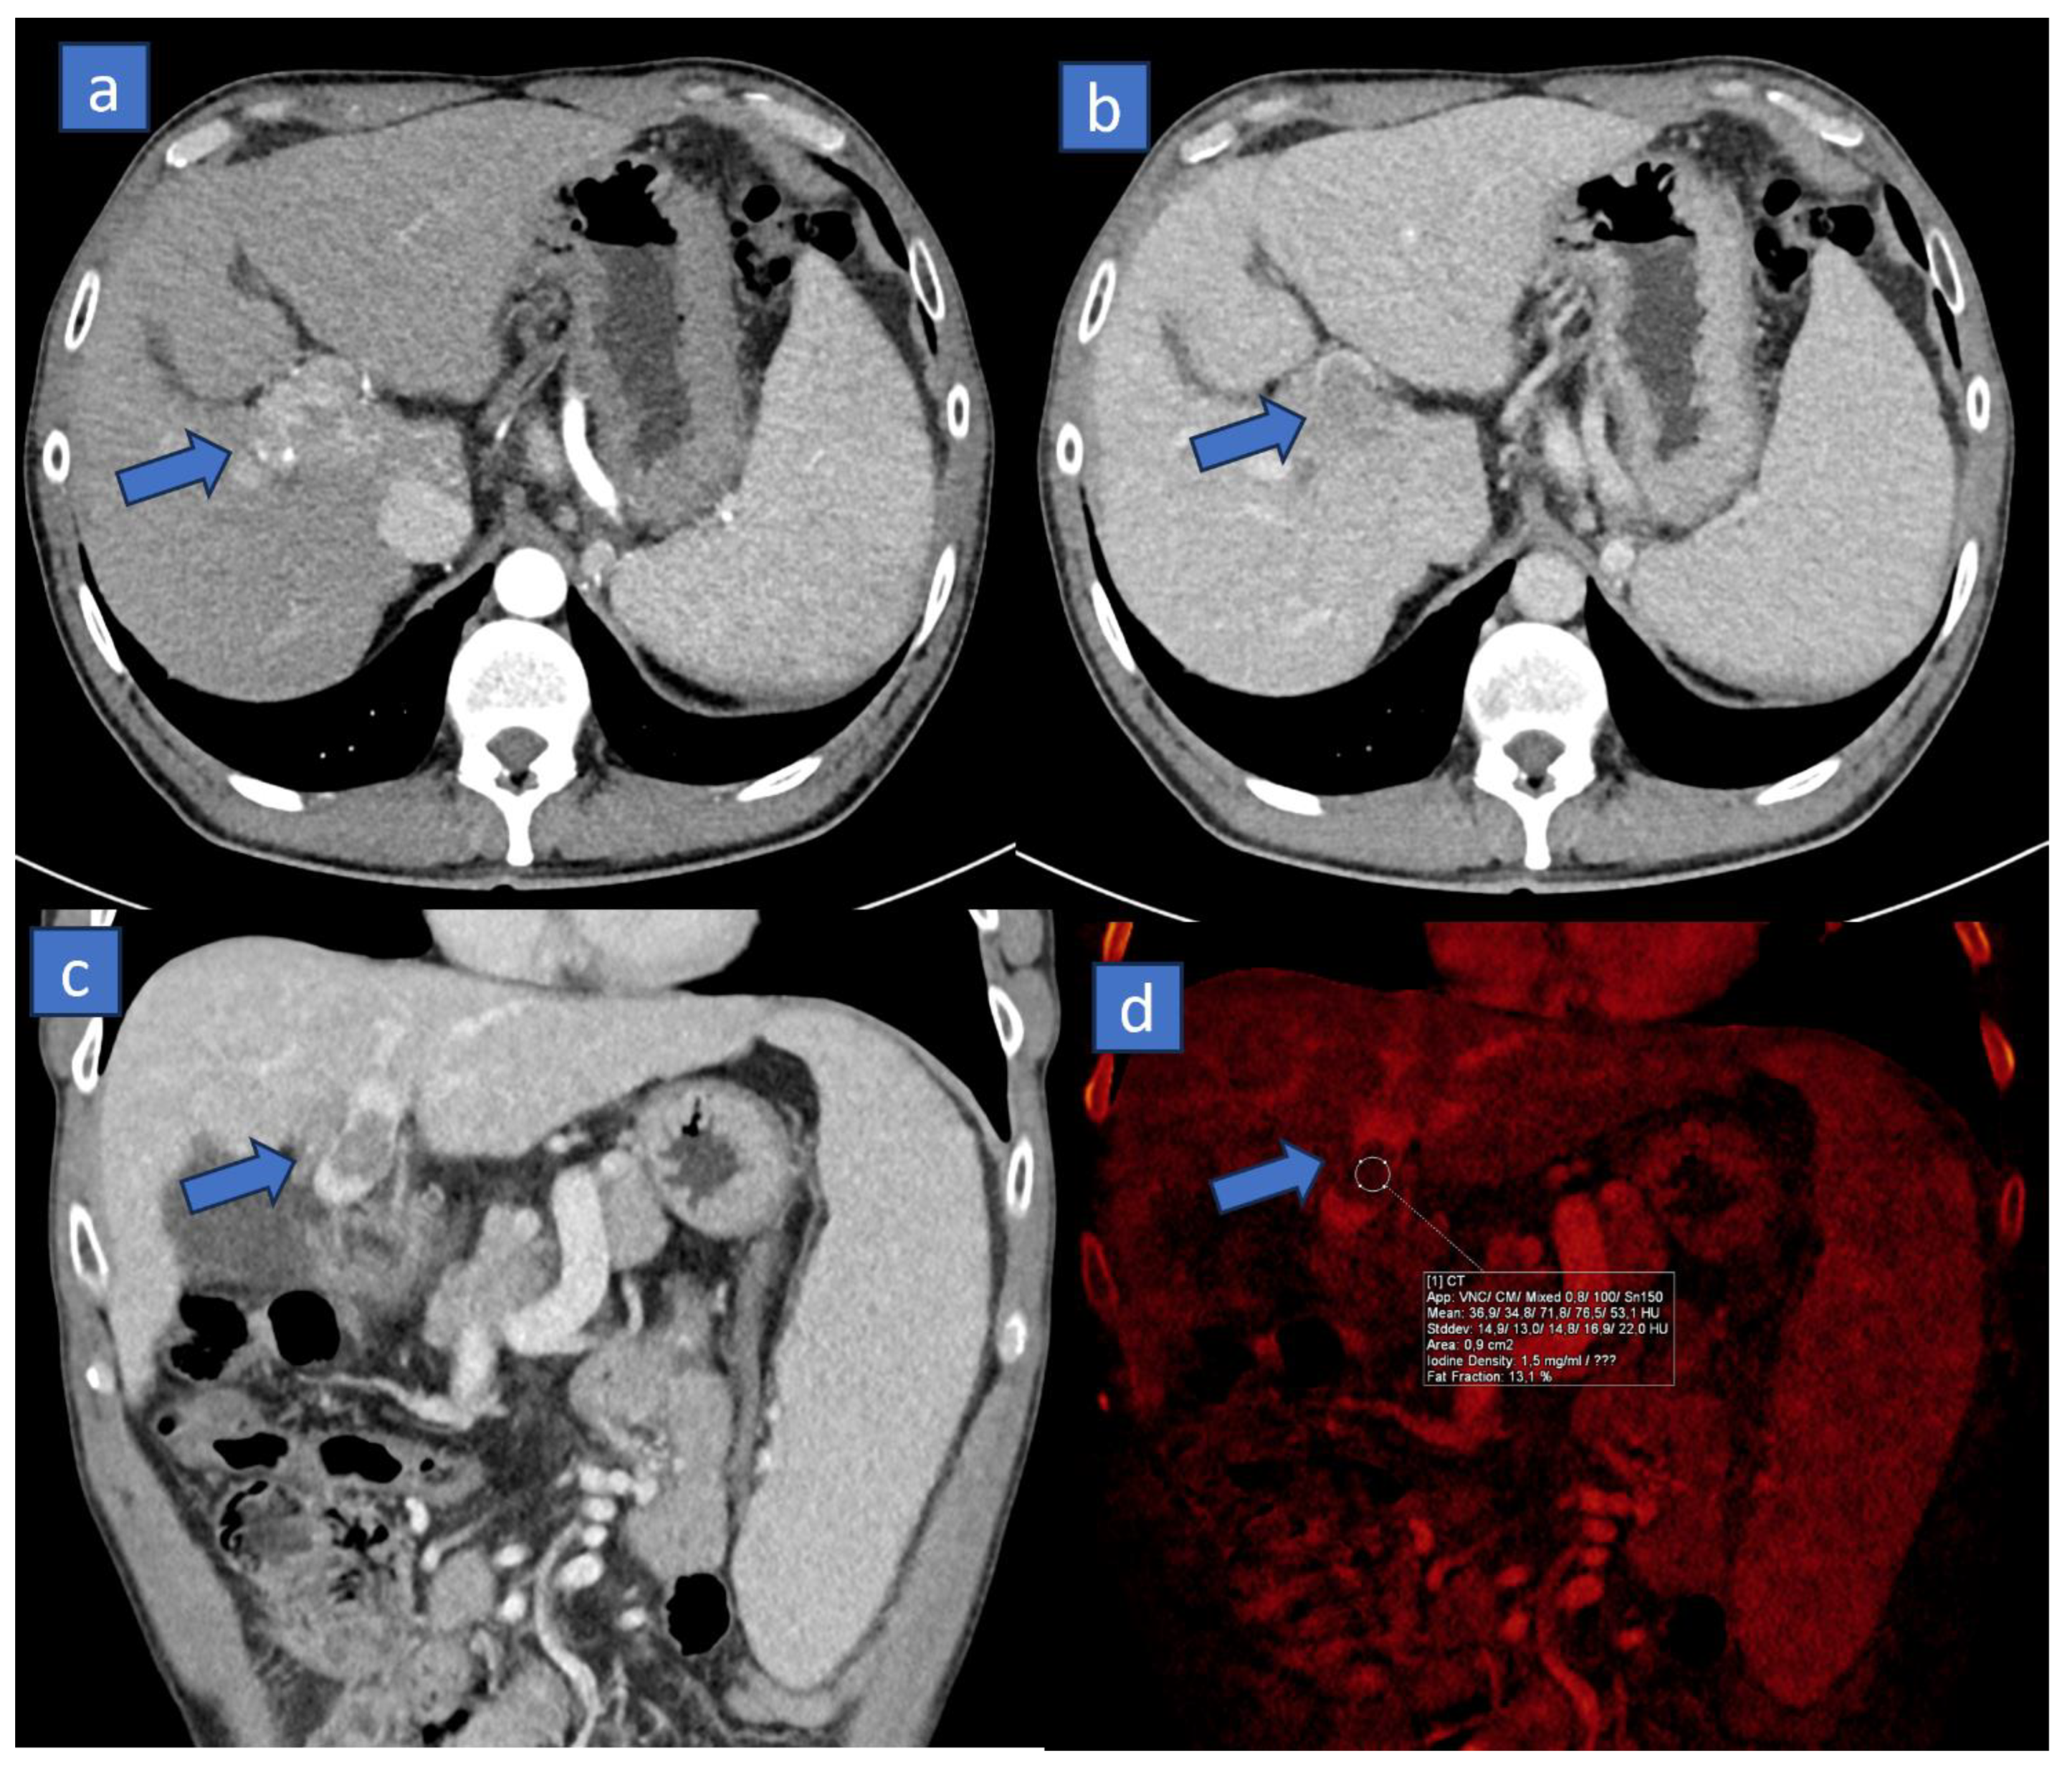

3. Iodine MAP

3.1. Applications